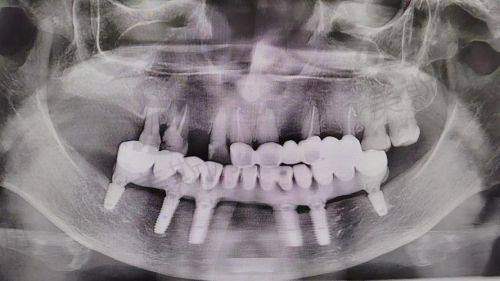

长春345口腔医院作为吉林国健医疗集团旗下的连锁牙科品牌,以“种植牙工厂店”为特色,4家连锁分院正规靠谱,在种植牙方面口碑良好。下面从技术与服务亮点来详细了解一下:

- 作为总院,设备齐全。在种植牙领域,擅长数字化导板种植,这种技术可以精细定位种植位置,提高种植的成功几率和正确性。对于中老年半口/全口修复也有丰富的经验,能够根据患者的具体情况制定个性化的修复方案。

- 地处市中 心,毗邻伪满皇宫博物院。主打即刻种植技术,患者当天就可以戴牙,大大节省了治疗时间,非常适合时间紧迫的上班族。这种技术对于医生的技术水平和医院的设备要求都比较高,而该分院能够开展此项技术,说明其在口腔种植领域有一定的实力。

- 配备鹰视激光仪,这一精良设备可以使创口愈合速度提升40%。在种植方面,擅长骨量不足种植,对于一些牙槽骨条件不好的患者也能提供有效的种植解决方案。同时,在青少年隐形矫正方面也有专长,能够根据青少年的生长发育特点和牙齿情况,制定合适的矫正方案。

- 各分院能够开展多种精良的口腔技术,如数字化导板种植、即刻种植、骨量不足种植、青少年隐形矫正、舒适微创种植、全口吸附性义齿修复等,这些技术的开展需要医生具备扎实的专精知识和丰富的临床经验。例如,数字化导板种植需要医生熟练掌握口腔CT数据的分析和导板的设计与应用;即刻种植技术要求医生在短时间内完成种植手术,并且确保种植体的稳定性和初期愈合成效。